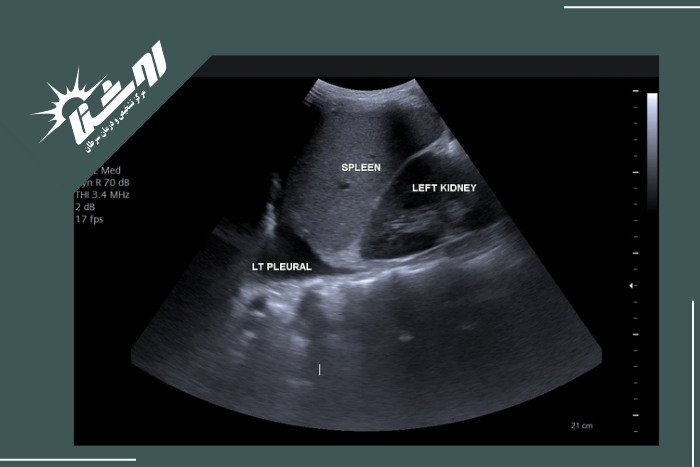

تشخیص آب آوردن ریه (پلورال افیوژن) با سونوگرافی

سونوگرافی قفسه سینه (اولتراسوند) یکی از بهترین ابزارها برای تشخیص وجود و میزان مایع در فضای پلور است. این روش با ارسال امواج صوتی با فرکانس بالا و دریافت بازتاب آنها تصویری زنده از ساختارهای داخل قفسه سینه ارائه میدهد. بهصورت خلاصه:

چون مایع امواج صوتی را به خوبی عبور میدهد در تصویر اولتراسوند به شکل ناحیهای تیره یا بدون اکو (آنهاکو) دیده میشود؛ این نخستین نشانهی وجود افیوژن است.

سونوگرافی حجم مایع را حتی در اندازههای بسیار کم (در حد ۵ تا ۱۰ میلیلیتر) نشان میدهد دقیقتر از عکس ساده قفسه سینه.

پزشک میتواند مشاهده کند که ریه در میان مایع «شناور» است یا خیر؛ این علامت ویژهی افیوژن آزاد است.